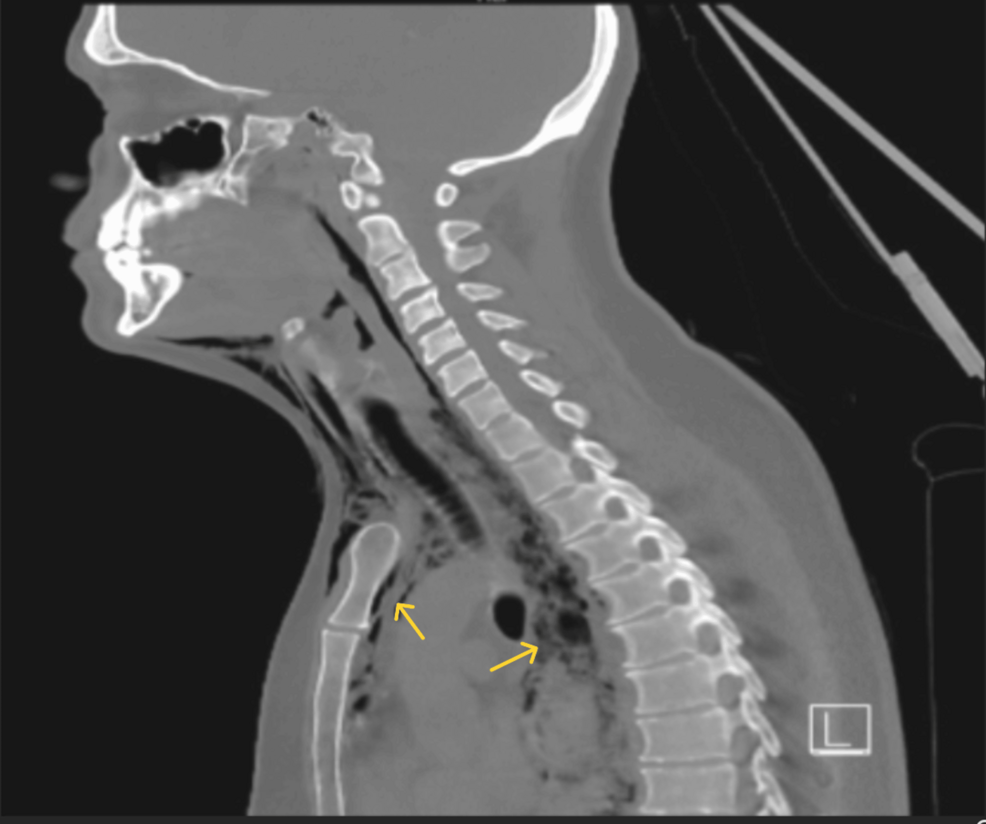

A 38-year-old male presented to the emergency department with acute, severe chest pain radiating to the back, accompanied by fever and shortness of breath. Initial assessment suspected a myocardial infarction, but ECG and cardiac enzyme tests were negative. Further examination revealed subcutaneous emphysema and pneumomediastinum, strongly suggesting esophageal perforation.

* Diagnostic Findings: A CT scan of the chest confirmed a small perforation in the distal esophagus. Esophagoscopy revealed meaningful esophageal inflammation and friability. Biopsies demonstrated a dense eosinophilic infiltrate – over 20 eosinophils per high-power field – consistent with Eosinophilic Esophagitis.